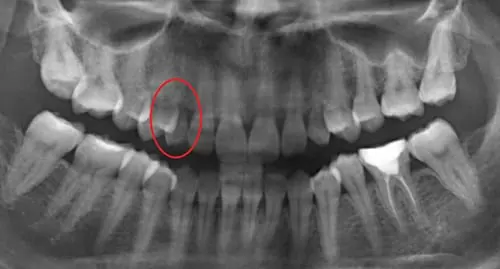

患者於初次來門診時,僅有乳牙之犬齒殘根附著於牙齦上。經X光片檢查,患者右上的犬齒有先天性缺牙。

植牙術前全口環頸式X光片